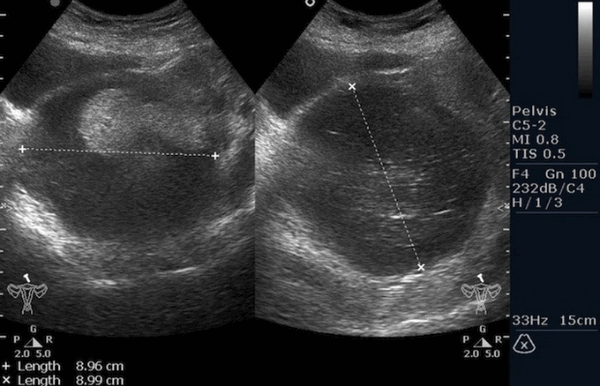

Рисунок 3. - тератома яичника а -УЗИ, б — МРТ.

- УЗИ. «Ультразвук» нужен для того, чтобы выявить первичный очаг как гонадной (в половых органах), так и внегонадной герминогенной опухоли. Его также проводят в ходе терапии, чтобы оценить ее эффективность.

![Тератома яичника (УЗИ малого таза)]()

Тератома яичника (УЗИ малого таза)